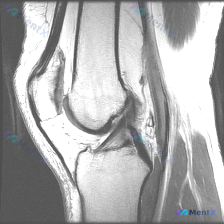

这是一份特殊的膝关节影像评估需求:输入描述提示存在软骨异常 (Chondral abnormality),提供1张膝关节矢状位MRI静态图像,我们先看影像学分析结果:

- 骨骼与软骨:股骨远端、胫骨近端、髌骨骨皮质完整,无骨折,无骨髓水肿;股骨髁、胫骨平台、髌股关节面软骨信号均匀,无局灶性缺损,无软骨下骨暴露。

- 韧带:前交叉韧带、后交叉韧带走行清晰,张力自然,连续性完整,无异常。

- 半月板与软组织:显示范围内半月板形态、信号正常,无撕裂;髌腱、股四头肌腱信号均匀连续;髌下脂肪垫无炎症水肿。

- 关节腔与其他:无明显关节积液,腘窝无囊肿或占位。

影像学总结:本次提供的单张矢状位MRI显示,膝关节各主要解剖结构形态、信号未见明确异常征象。